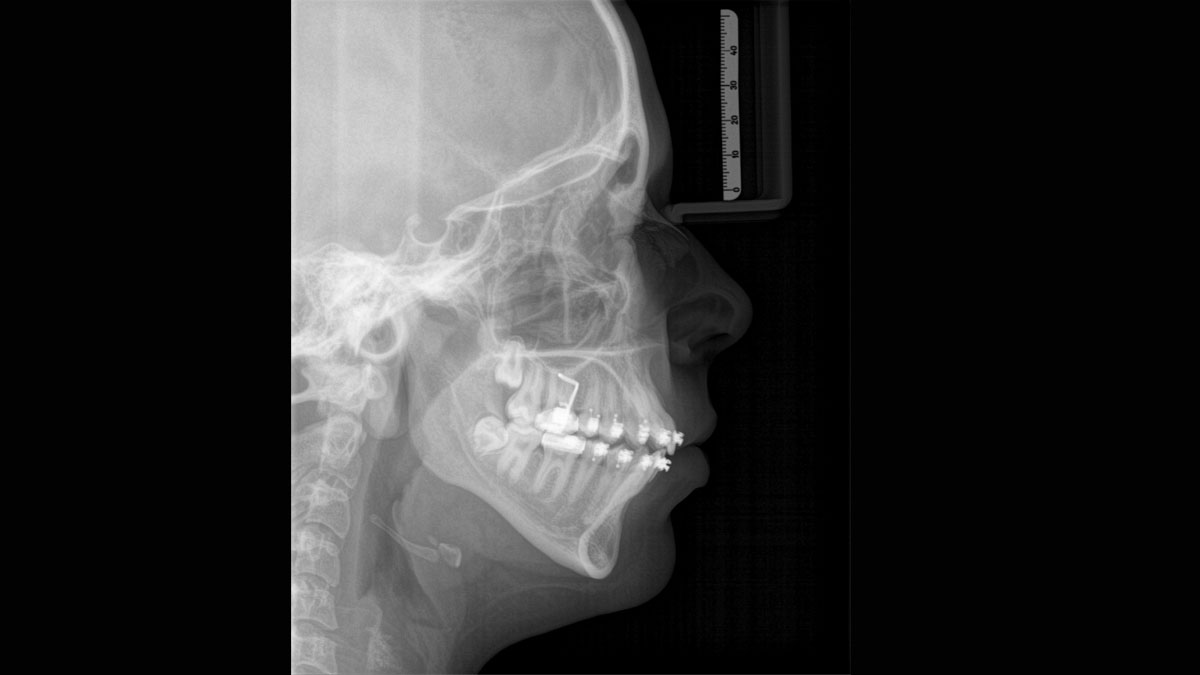

Der Autofokus erzeugt aus mehreren tausend Einzelbildern automatisch eine beeindruckende scharfe Panorama-Röntgenaufnahme

Nicht nur wegen meines Interesses an Technik finde ich die Kombination aus Direktumwandlung und rekonstruktivem Autofokus im Orthophos SL wirklich spannend. Die daraus resultierenden präzisen Bilder eignen sich hervorragend für die Interpretation. In Kombination mit der Volumenauswahl in 3D haben wir einen universell einsetzbaren Diagnostikpartner für unsere Praxis.“

Marcin Wojtunik, Facharzt für Mundchirurgie, Pfronten, Deutschland

Eine Röntgenaufnahme muss sofort diagnostizierbar sein. Der Autofokus hilft dabei erheblich. Orthophos SL erfasst mehrere tausend Einzelbilder in einem Zyklus und erkennt automatisch scharfe Bereiche, um ein gleichmäßig scharfes Gesamtbild zu erzeugen. Der intelligente Autofokus erfordert keine manuellen Arbeitsschritte vor und nach der Erfassung.